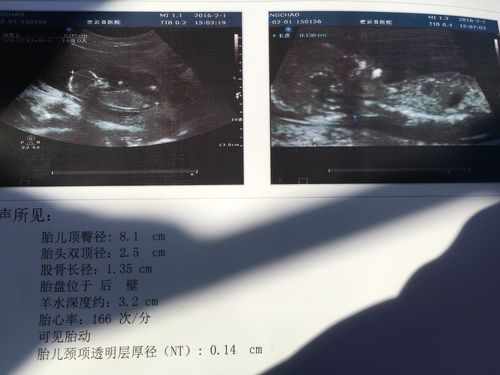

怀孕十三周胎儿性别图

怀孕十三周胎儿性别图,十六周胎儿性别区别图

宝妈我十三周nt你会看吗?

13周b超可看性别吗?有宝妈会看的不

孕13周,很好奇宝宝的性别,有人会看吗